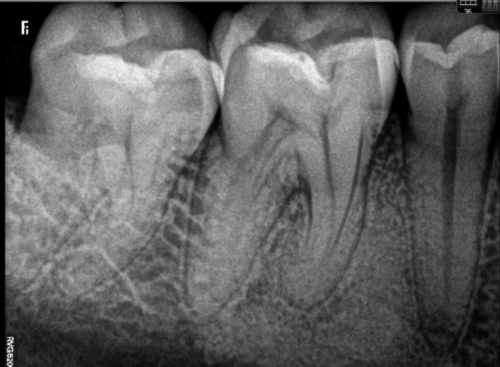

Get a precise consultation with advanced digital X-rays that help us detect issues early and plan the best treatment for your smile.

Our portable X-ray unit allows us to quickly capture diagnostic images during your consultation, ensuring faster evaluations and seamless treatment planning. Whether it’s for detecting cavities, assessing root conditions, or evaluating bone health, our X-ray facility ensures accuracy without delay.

With zero need for repositioning or multiple visits, patients enjoy a more comfortable, time-saving experience while our team gets the detailed data needed for expert care.